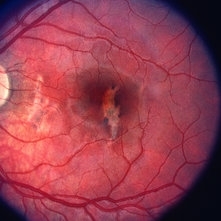

Traumatic Mac Scar

May 2 2013 by Henry J. Kaplan, MD

Traumatic stellate shaped subretinal macular scar.

Condition/keywords: blunt trauma, macular scar